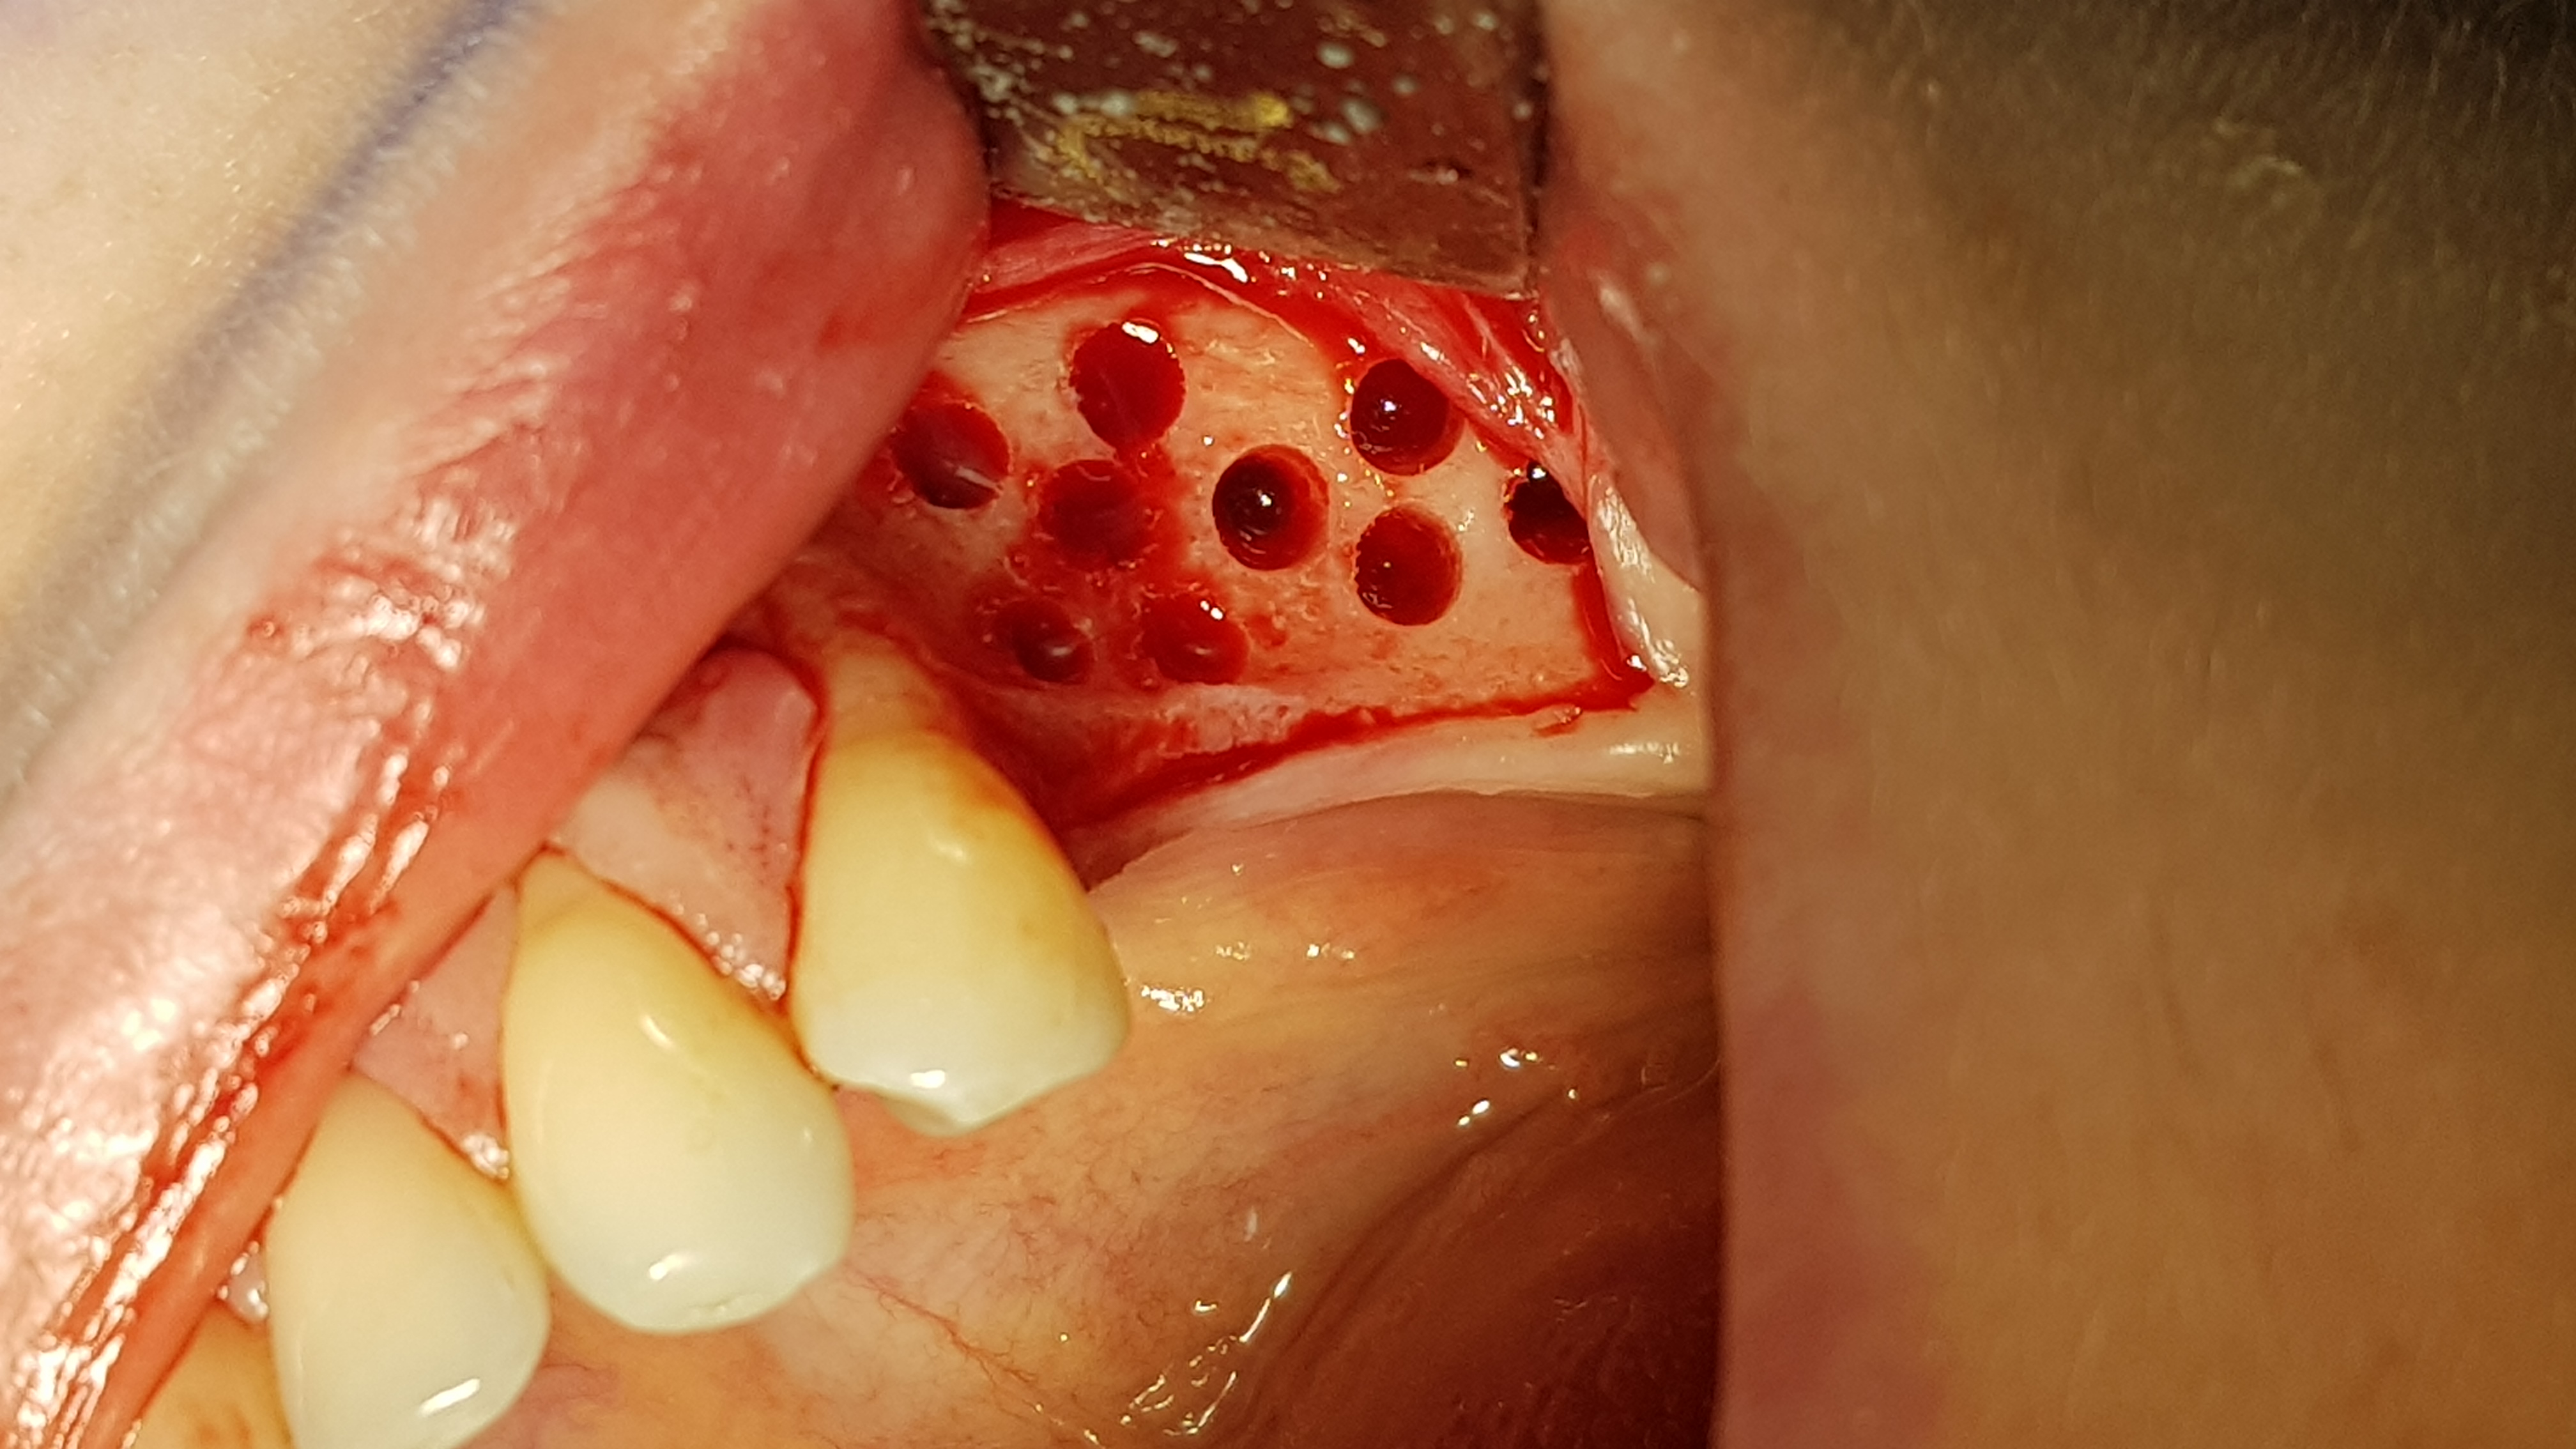

Następnie wykonano otwory trepanacyjne w blaszce korowej kości o średnicy około 3 mm dochodząc do kości gąbczastej (ryc. 7). Taka średnica jest zalecana przez producenta dla lepszej retencji i utrzymania kształtu cementu regeneracyjnego w takim ubytku. Następnie po aktywacji umieszczono i uformowano cement na przygotowanej powierzchni kości (2 cm3) (ryc. 8).

Ryc 8. Uformowanie cementu na powierzchni wyrostka.   Ryc 9. Zaopatrzenie rany.

Kształt opracowano ręcznie przy użyciu raspatora i sterylnych gazików 5/5 cm. Następnie ranę przykryto płatem bez podcinania okostnej, a jedynie rozciągając go o kilka milimetrów dzięki wykorzystaniu pewnej elastyczności błony śluzowej. Ranę zaopatrzono szwami (polidioksanon 4-0, igła okrągła kłująca, długość 16 mm, profil ½ koła oraz nylon 5-0, igła odwrotnie tnąca, długość 12 mm, profil 3/8 koła) (ryc. 9). Pacjentka po zabiegu stosowała standardową antybiotykoterapię doustną (Amoksycylina 1.0 g co 12h 7 dni) oraz miejscowo płukanie jamy ustnej roztworem chlorcheksydyny. Rana goiła się prawidłowo, szwy usunięto w 10 dobie po zabiegu oraz wykonano kontrolne projekcje rtg, które wykazały prawidłowe utrzymanie cementu na wyrostku (ryc. 6-12).